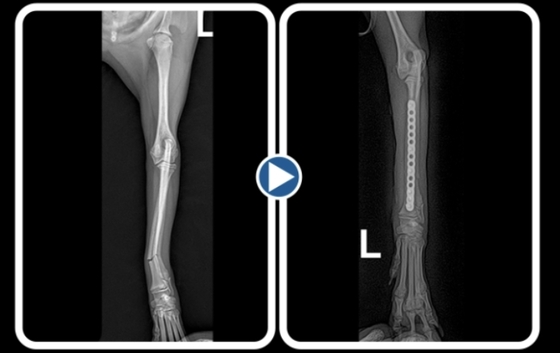

성인 무릎 높이에서 뛰어 내려 착지하다 골절이 발생한 반려견 방사선 검사 이미지(로얄동물메디컬센터 제공)© 뉴스1

의료진은 전신 상태를 평가한 뒤 플레이트를 이용한 내고정 수술을 진행했다. 소형견의 요척골은 직경이 매우 얇아 플레이트 선택과 스크 각도가 유합 성공의 핵심으로 꼽힌다. 길이와 각도를 정확히 맞추지 못하면 평생 파행이 남을 수 있기 때문이다.

플레이트를 이용한 반려견 요척골 골절 수술 방사선 사진(로얄동물메디컬센터 제고) © 뉴스1

수술 후 입원 치료를 거쳐 퇴원한 뒤에는 철저한 활동 제한과 정기적인 방사선 추적 검사가 병행됐다. 요골이 먼저 붙고 척골이 늦게 유합되는 경우가 흔해 회복 과정에서 세심한 관리가 필요하다는 설명이다. 수술 약 2주 차에는 다리를 디디려는 모습이 관찰됐다. 1개월 차 검사에서는 통증 반응 없이 정상적인 골 회복이 확인됐다.